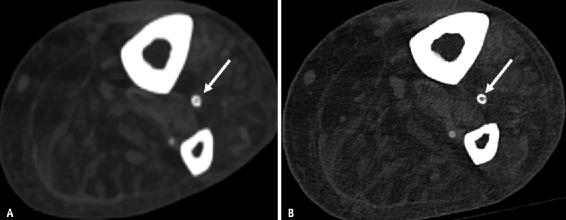

开花(Blooming )伪影是由具有不同组织的体素中衰减值的部分容积平均引起的图像伪影,使得难以分辨小于体素的对象。由于CT系统的空间分辨率有限,钙化晕状伪影是心血管检查中常见的伪影。开花伪影是心血管成像中的一个重要挑战,尤其是在具有钙或支架的小血管(例如冠状动脉、远端动脉)中,因为放射科医生试图将这些结构与造影剂填充的管腔区分开。因此,钙化斑块(以及金属支架)似乎大于其真实尺寸,导致对管腔狭窄的高估,这可能导致不适当的临床管理。PCD可以通过多种方式解决钙化的开花问题。随着空间分辨率的提高,可以通过减少体素大小和部分容积来改善钙化的晕状伪影,从而提高密集血管钙化患者狭窄评估的准确性(图12)。或者,也可以通过增加X射线能量降低体素的平均衰减来减少钙化晕状伪影,这可以在PCD-CT中利用高能VMI实现。最后,可以使用材料分解算法从图像中分离钙化,该算法可以使用多能量信息创建,潜在地提供管腔狭窄的更精确估计(图13)。

图12 74岁男性患者,患有已知的外周动脉疾病。A、B 外周动脉疾病患者的轴位重建在能量积分探测器CT上显示胫前动脉中有钙晕(箭头A)。与能量积分探测器CT重建(A)相比,同一患者在同一水平上的光子计数探测器CT重建显示出胫骨前动脉(箭头,B)中钙斑的可视化显著改善,因此可以更好地评估管腔直径。

图13 钙分离算法。A、外周动脉疾病患者的轴位能量积分探测器CT重建显示右股总动脉中有致密钙化斑块(箭头)。B、使用专用钙分离算法对同一患者进行的轴位光子计数探测器CT重建显示了钙化斑块的去除(箭头)。